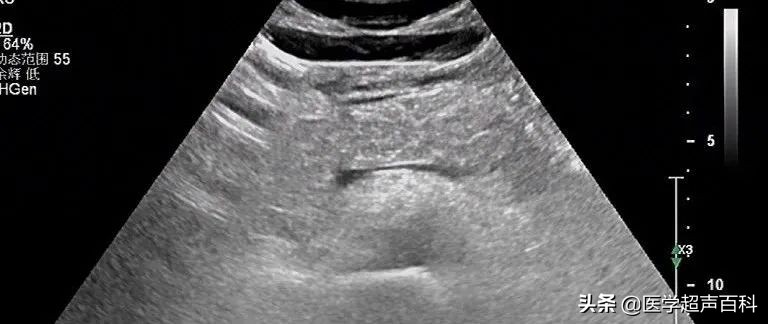

水肿型胰腺炎:胰腺弥漫性增大,边缘形态规整,内部回声减低,胰腺后方血管受压迫显示不清

(1)胰腺弥漫性或局限性增大,可失去正常形态,轮廓不清。

(2)内回声减低,呈弥漫分布的弱点状,中间有强弱不均、形态不整、边界不清的片状回声。严重水肿时呈透声暗区,似囊肿声像图。